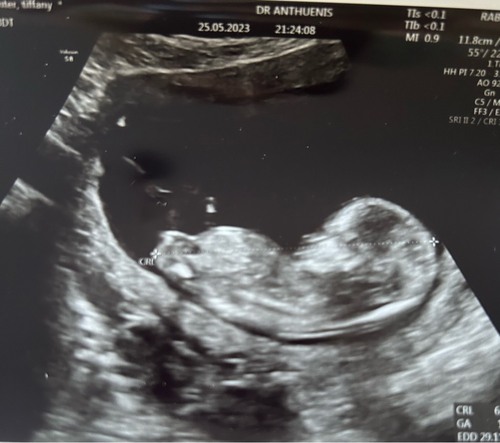

Toch even dubbelchecken… wat zien jullie hier?

Meisje

Goed om te lezen dat jullie hetzelfde zien 😍🩷